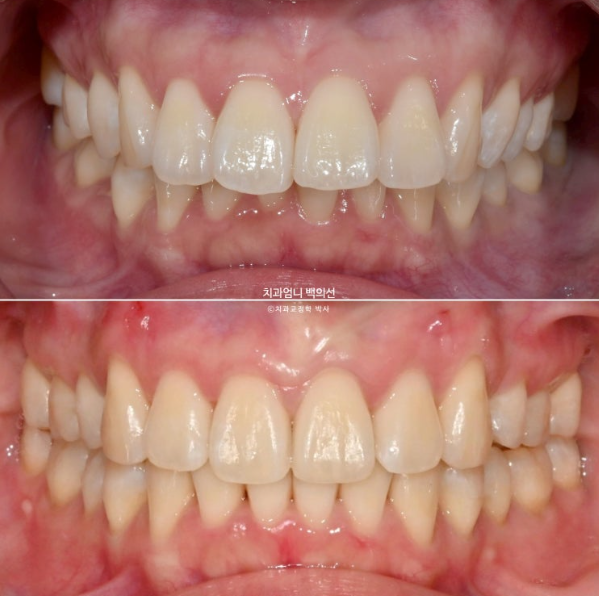

정면을 보시면 윗니가 아랫니를 많이 덮고 있습니다.

아랫니가 거의 보이지 않습니다.

이런 부정교합을 과개교합 이라고 합니다.

개선된 과개교합과 일치된 중심선

앞니 뻗침도 많이 좋아졌습니다.

23.02-25.01

전 후 비교입니다.

총 치료기간은 1년 11개월이고 실제 장치를 낀 기간은 1년 9개월입니다.